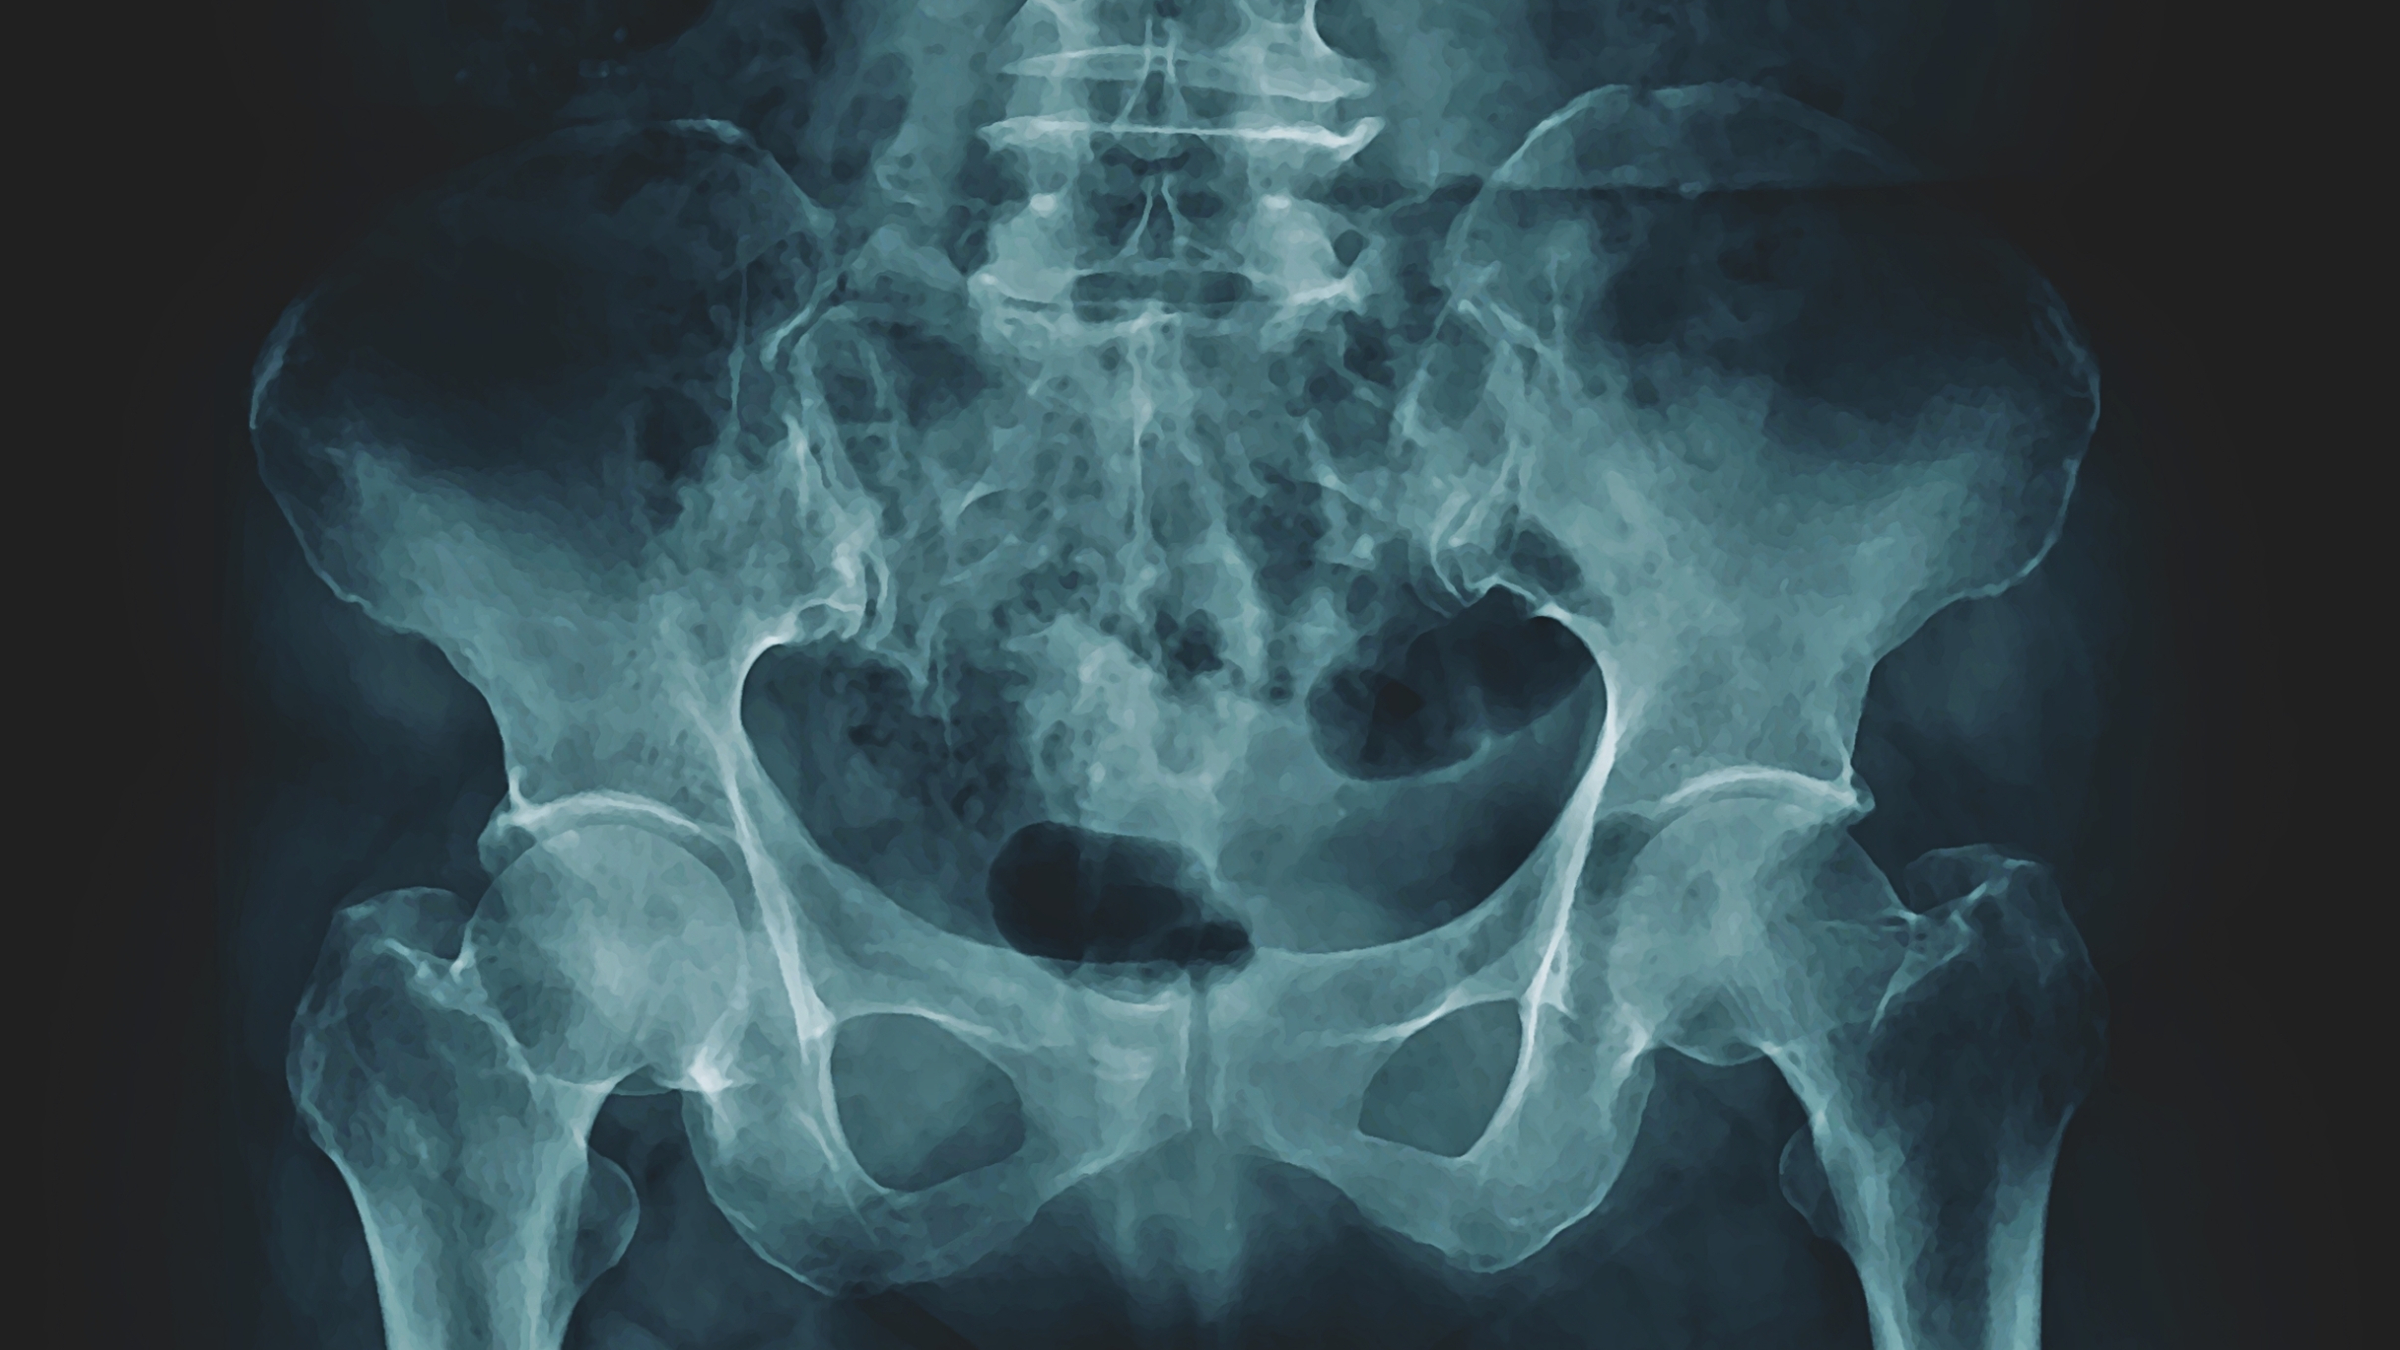

X-ray of a pelvis.

A 2023 study claims cycling can cause significant bone density loss in as little as a year. Is there more to the story?